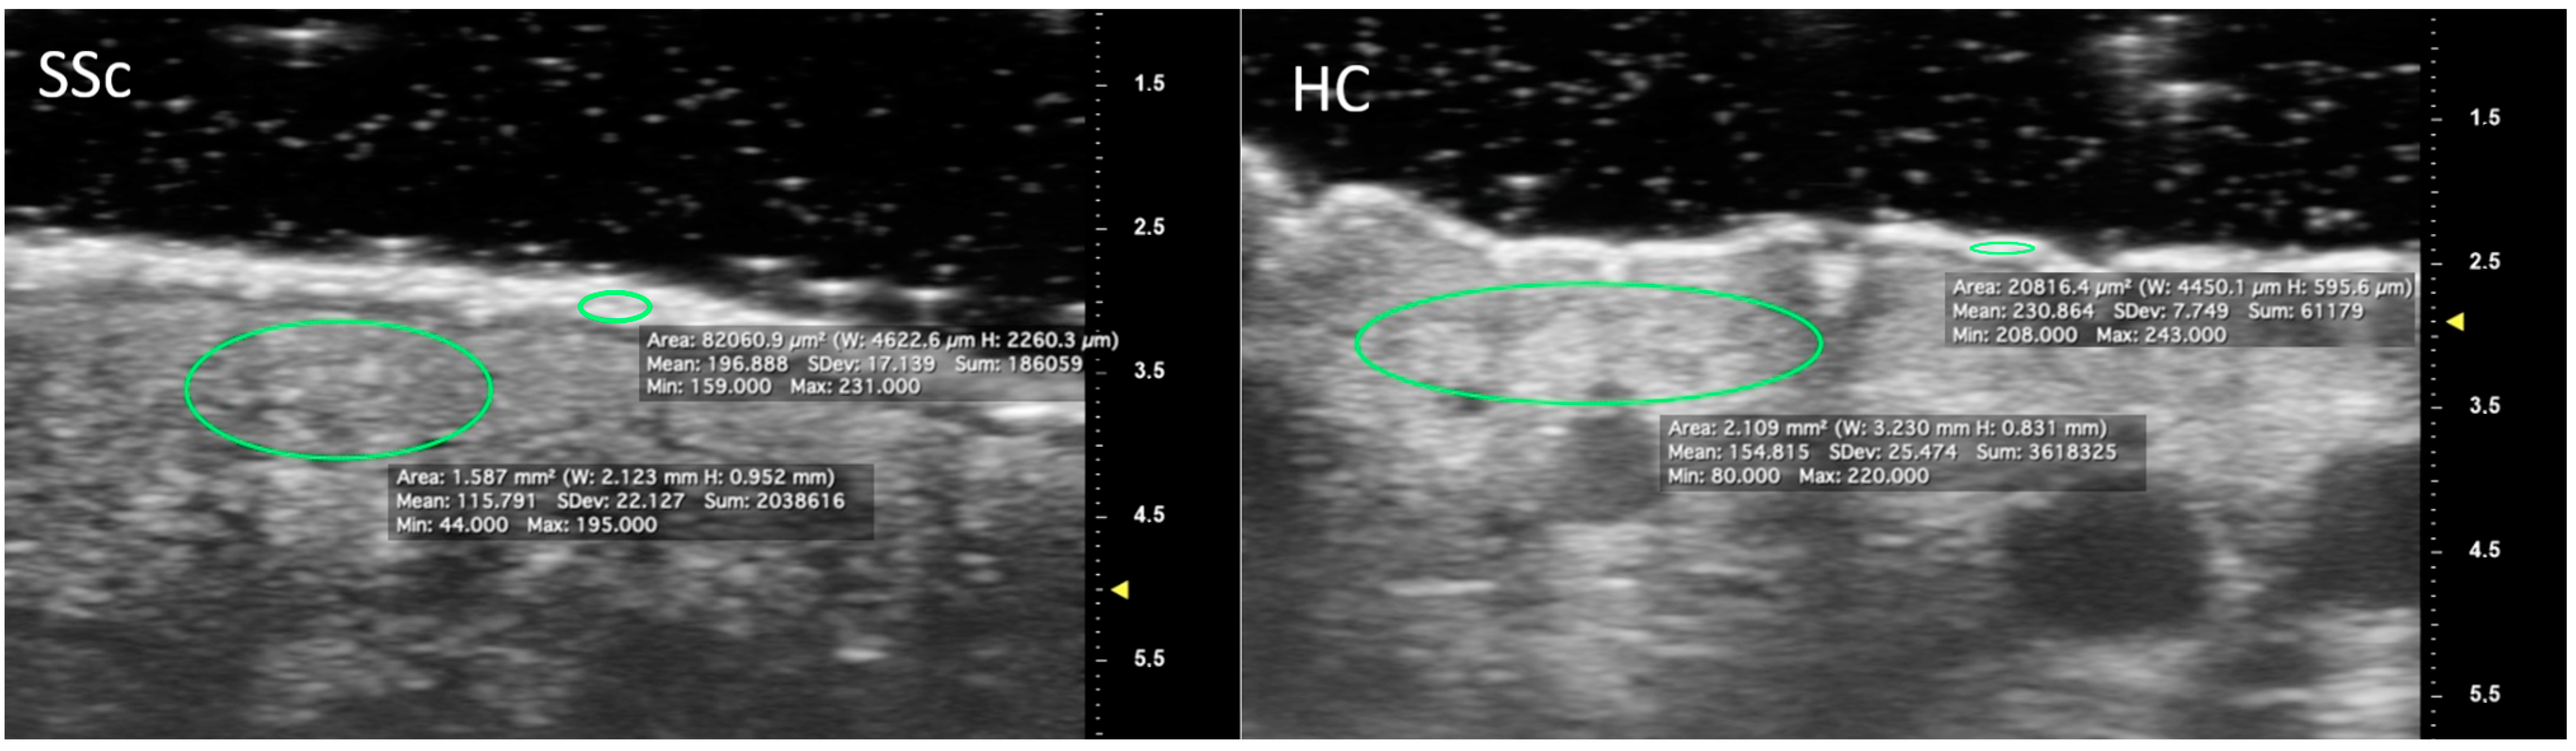

The SSc group also presented lower epidermal MGV at DP, IP and PP (p = 0.01 for all). Similarly, low values of dermal MGV reached statistical significance at DP (p < 0.001), IP (p = 0.006) and PP (p = 0.04)—Figure 3. When UHFUS results were diversified according to skin subset, both lcSSc and dcSSc reconfirmed a significantly thicker epidermal layer than HC for all the regions of interest. Noteworthy, when considering MGV differences between cutaneous subsets and HC, statistically significant lower values were detected for both skin subsets only at the dermal layer of DP (p = 0.001 for lcSSc; p = 0.008 for dcSSc) and IP (p = 0.05 for lcSSc; p = 0.01 for dcSSc).

Figure 3.

Measurement of epidermal and dermal grayscale values using ROIs positioned at the intermediate phalanx of the second finger. Note the reduction in the mean grayscale value in the SSc patient compared to the control subject in the epidermal and dermal areas.